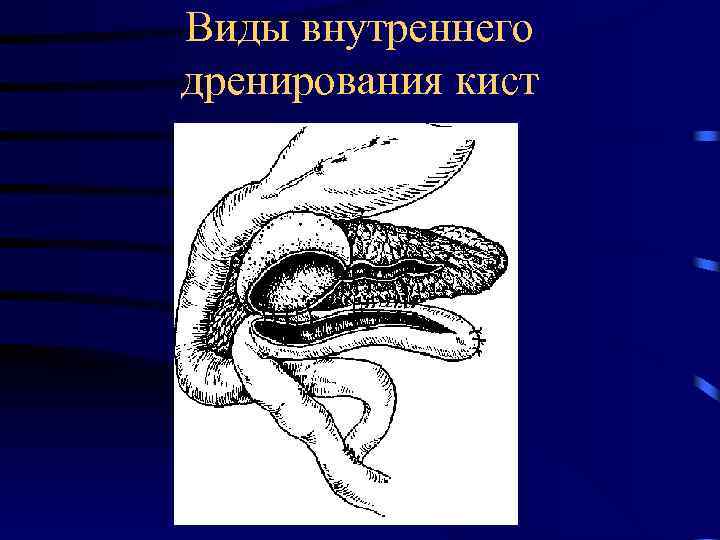

Виды внутреннего дренирования кист

Виды внутреннего дренирования кист